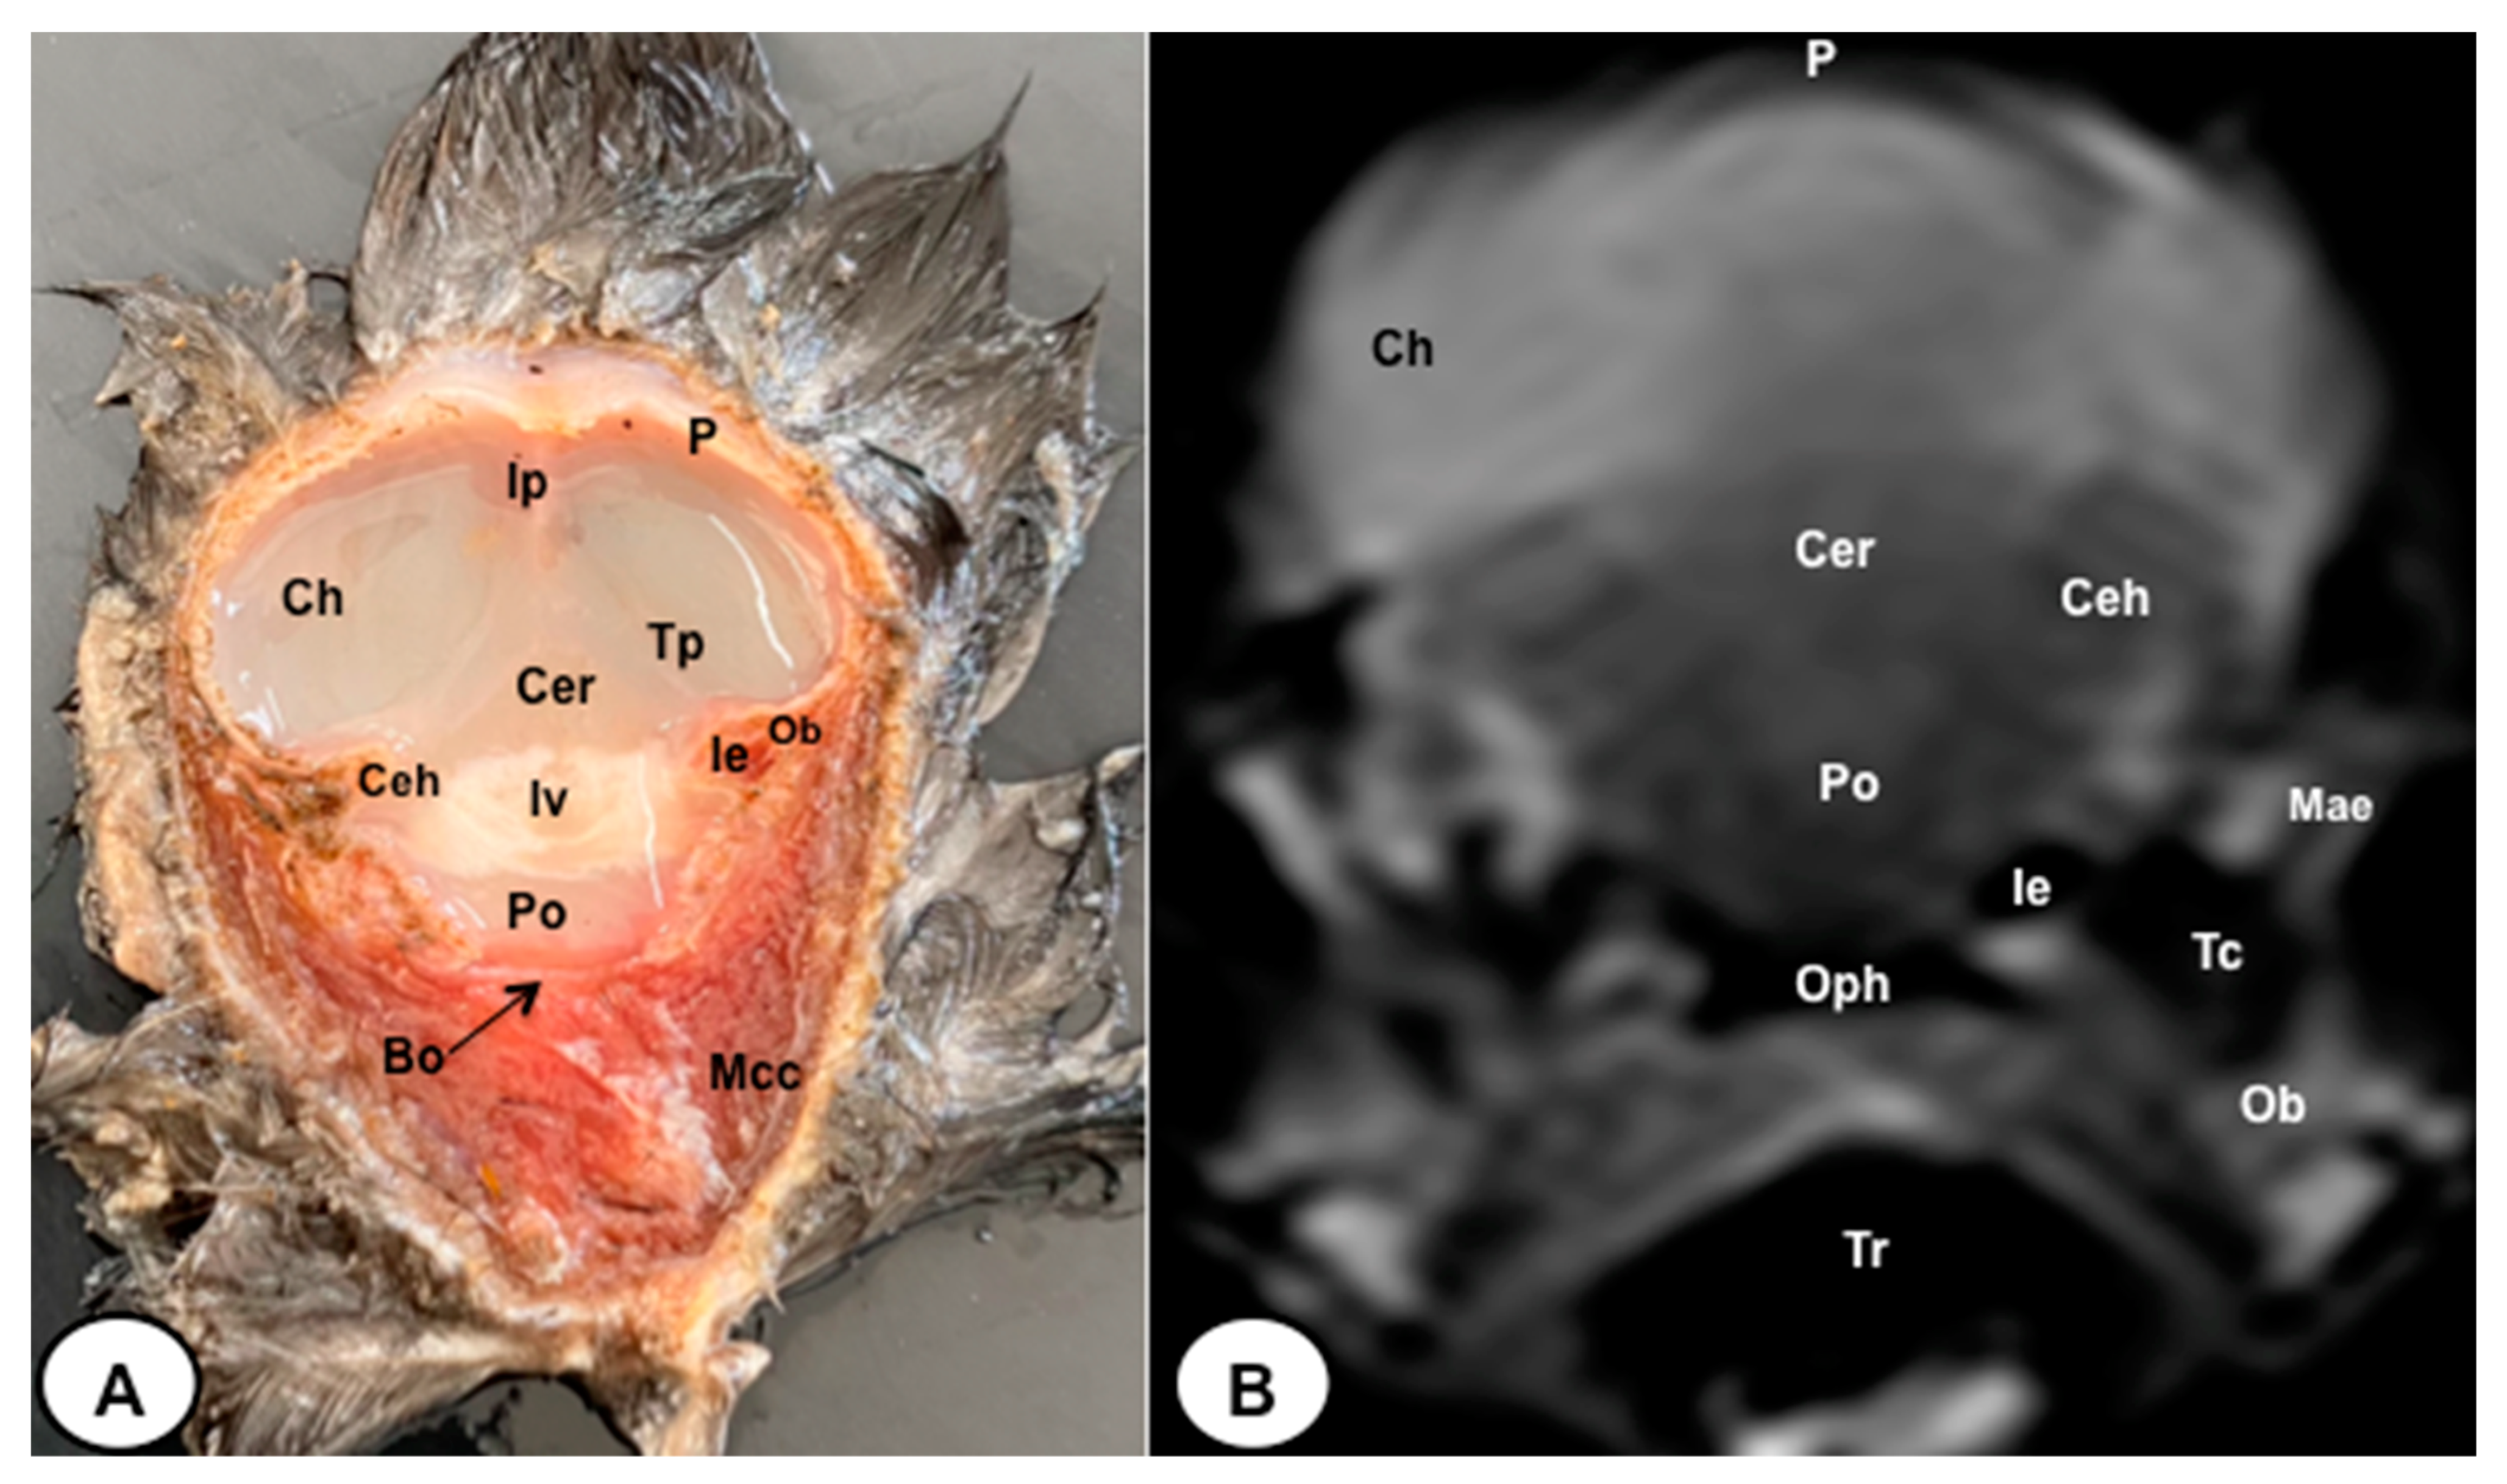

3.1. Anatomical Sections

3.2. Magnetic Resonance Imaging (MRI)